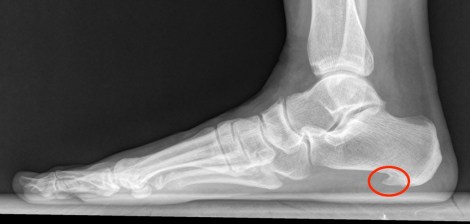

Omdat ik hypermobiel ben, ondersteunen te lange pezen mijn voetspieren niet goed. Het gevolg is dat de bindweefselband (de plantar fascia) onder de voet teveel uitrekt waardoor er micro scheurtjes in ontstaan. Met een peesplaatontsteking bij de aanhechting op het hielbot (fasciitis plantaris) als gevolg. Die aanhechtig op het hielbot kan ook verkalken en dan heb je er hielspoor bij. Die verkalking behandelen sommige fysiotherapeuten met shockwave therapie, waarbij je voeten behandeld worden met een soort niersteenvergruizer. Ik heb verschillende sessies gehad maar er geen baat bij gehad.